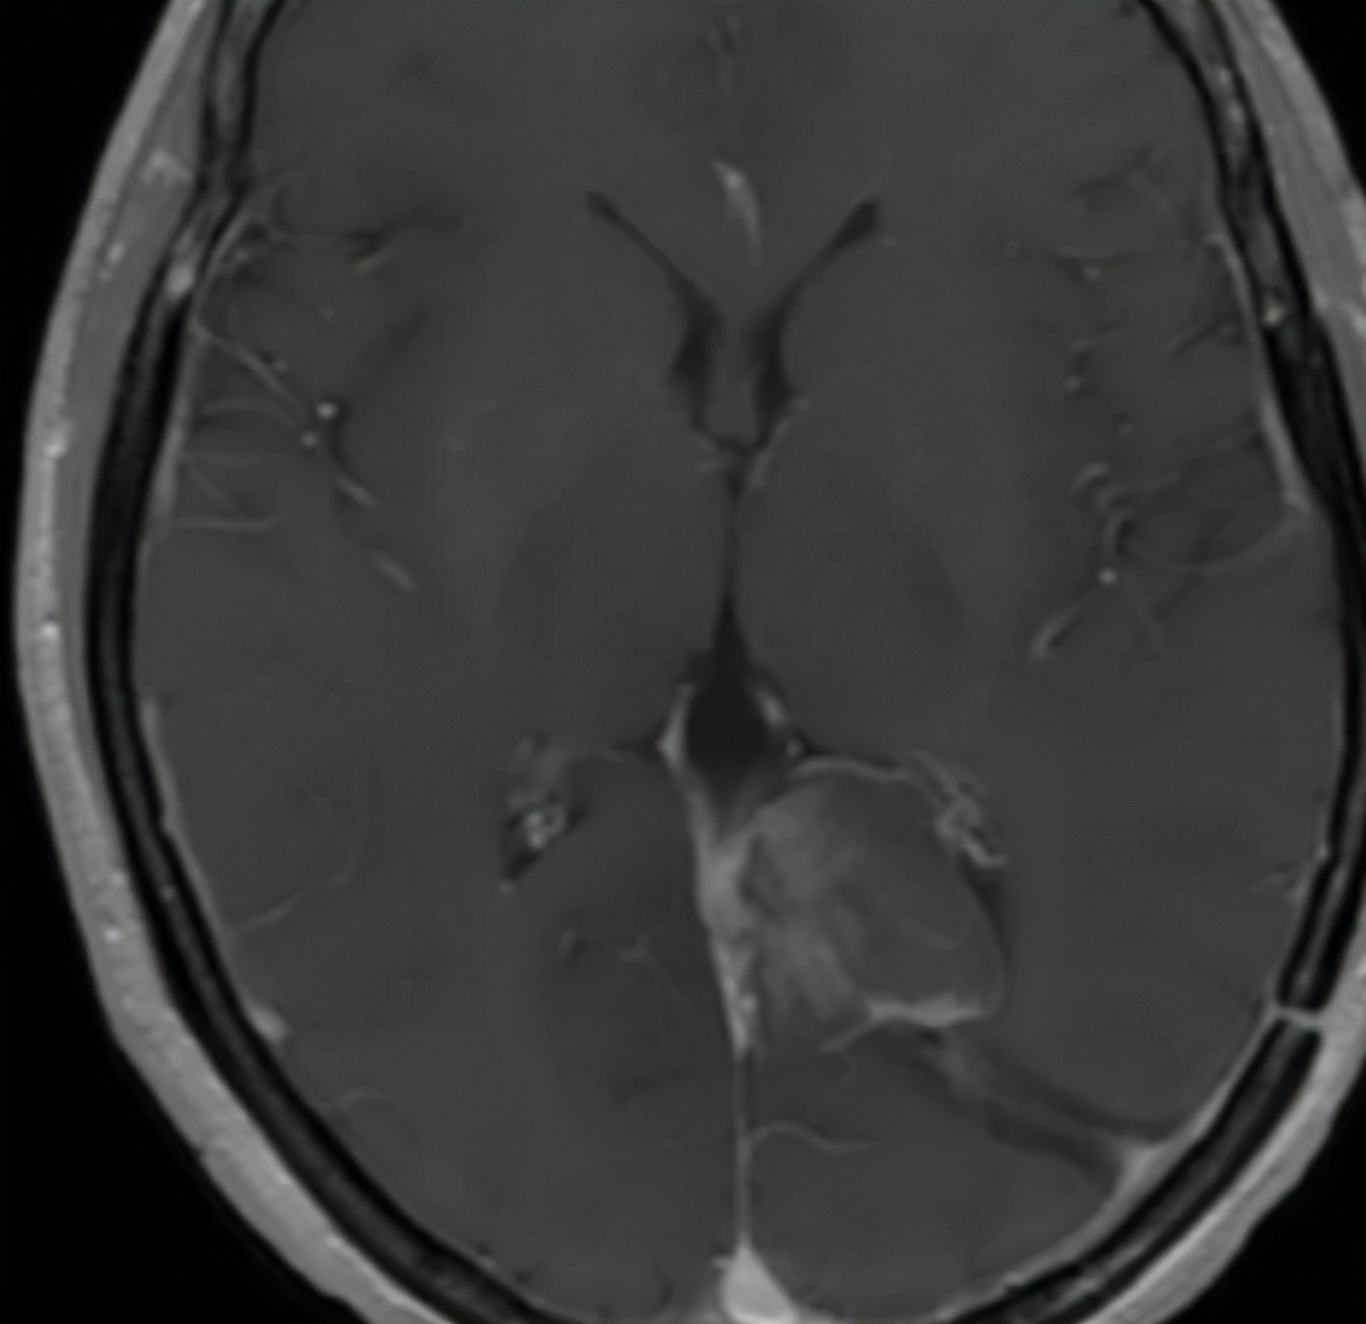

会不会是手术切除的标本中有肿瘤细胞,但是病理医生遗漏了呢?所以病人带着以前手术切除的病理标本来到广州中山大学附属肿瘤医院进行病理会诊,但也仅仅是看到胶质增生的改变,同样没有看到肿瘤细胞,治疗再次陷入困境。神经外科柯超医生团队通过分析病人手术后复查的磁共振片发现,病变还是显现比较典型的恶性肿瘤特征,之所以病理诊断无法明确,很可能是取材的部位不在肿瘤核心区域,所以病理医生难以诊断。

为了解决这个问题,建议病人再次手术,更多的切除肿瘤组织,一方面可以有更多核心的肿瘤组织标本便于诊断,另一方面也可以减少肿瘤体积,提高后续治疗的效果。经过这几个月的辗转,病人也理解了目前治疗的困境,选择了再次手术治疗,手术后顺利出院,手术中快速病理诊断考虑胶质瘤,2周后的常规病理诊断与之前的分析是一致的,是胶质瘤中的星形细胞瘤类型,局部呈间变性改变,也就是说是属于恶性胶质瘤中的一种。这样病人就能开始正规的放化疗控制肿瘤的生长与复发了。广州中山大学附属肿瘤医院神经外科柯超主诊教授指出,病理诊断结果是制定脑肿瘤个体化治疗方案的最重要依据,但是临床医生不能片面的只看某一种诊断结果,需要综合分析辩证看待各种检查结果,才能为脑肿瘤病人制定最佳治疗方案。